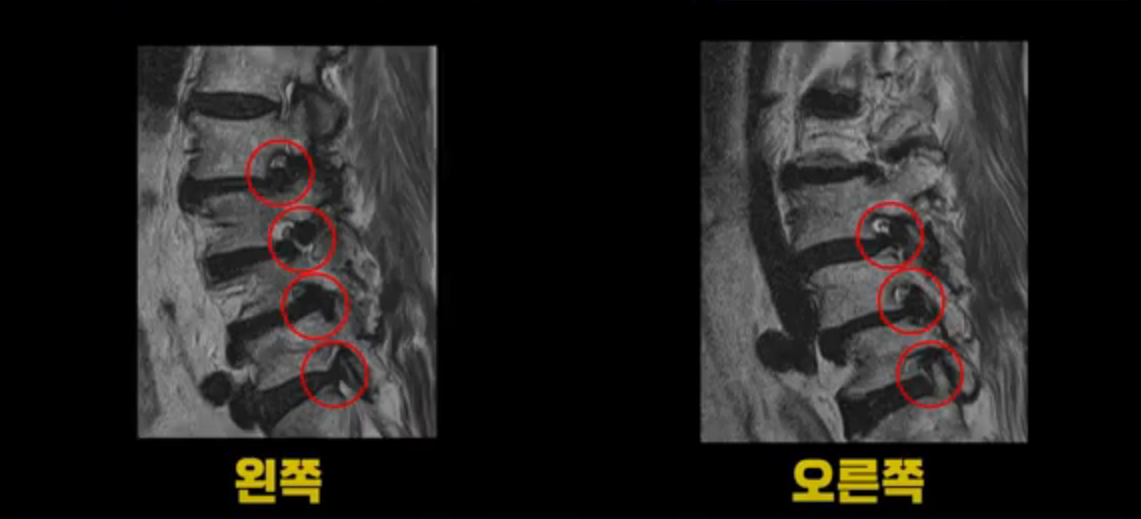

이 환자분 MRI를 보면서 더 자세히 설명 드리겠습니다. 이분은 허리의 다섯 마디가 다 안 좋은 환자분입니다. 84세 고령의 나이에 이렇게 여러 마디가 안 좋으면 대학병원에서도 수술이 어렵다는 얘기를 듣는 경우가 많습니다. 또 수술을 하더라도 결과가 안 좋을 수 있다는 얘기를 들을 가능성이 높습니다.

보시다시피 허리 다섯 마디 전부가 다 퇴행되어 있고,

두 마디에 전방전위증이 있고,

2번 3번,

3번 4번,

4번 5번에 중심성 협착이 심하고

거의 모든 추간공 즉, 신경가지가 좌우로 빠져나가는 구멍이 다 좁아져 있습니다.